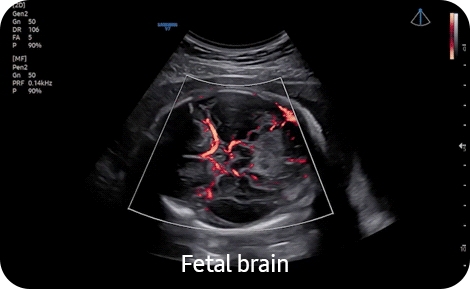

• Высокочувствительный направленный энергетический допплер S-Flow позволяет визуализировать даже самые мелкие сосуды

Направленный энергетический допплер:

Да